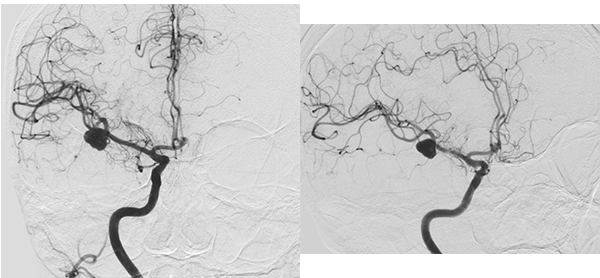

Figura 1:

A nivel del surco silvano derecho y en relación a la arteria cerebral media homolateral, se evidencian imágenes de baja señal en secuencia de gradiente eco (GRE) de aspecto sacular (A), en secuencia FLAIR se observa a nivel del surco Silviano en territorio de la arteria cerebral media derecha imagen hipointensa de forma sacular sugestiva de probable formación aneurismática, adyacente a la misma se aprecia hiperintensidad en parénquima cerebral sugestiva de edema (B y C).